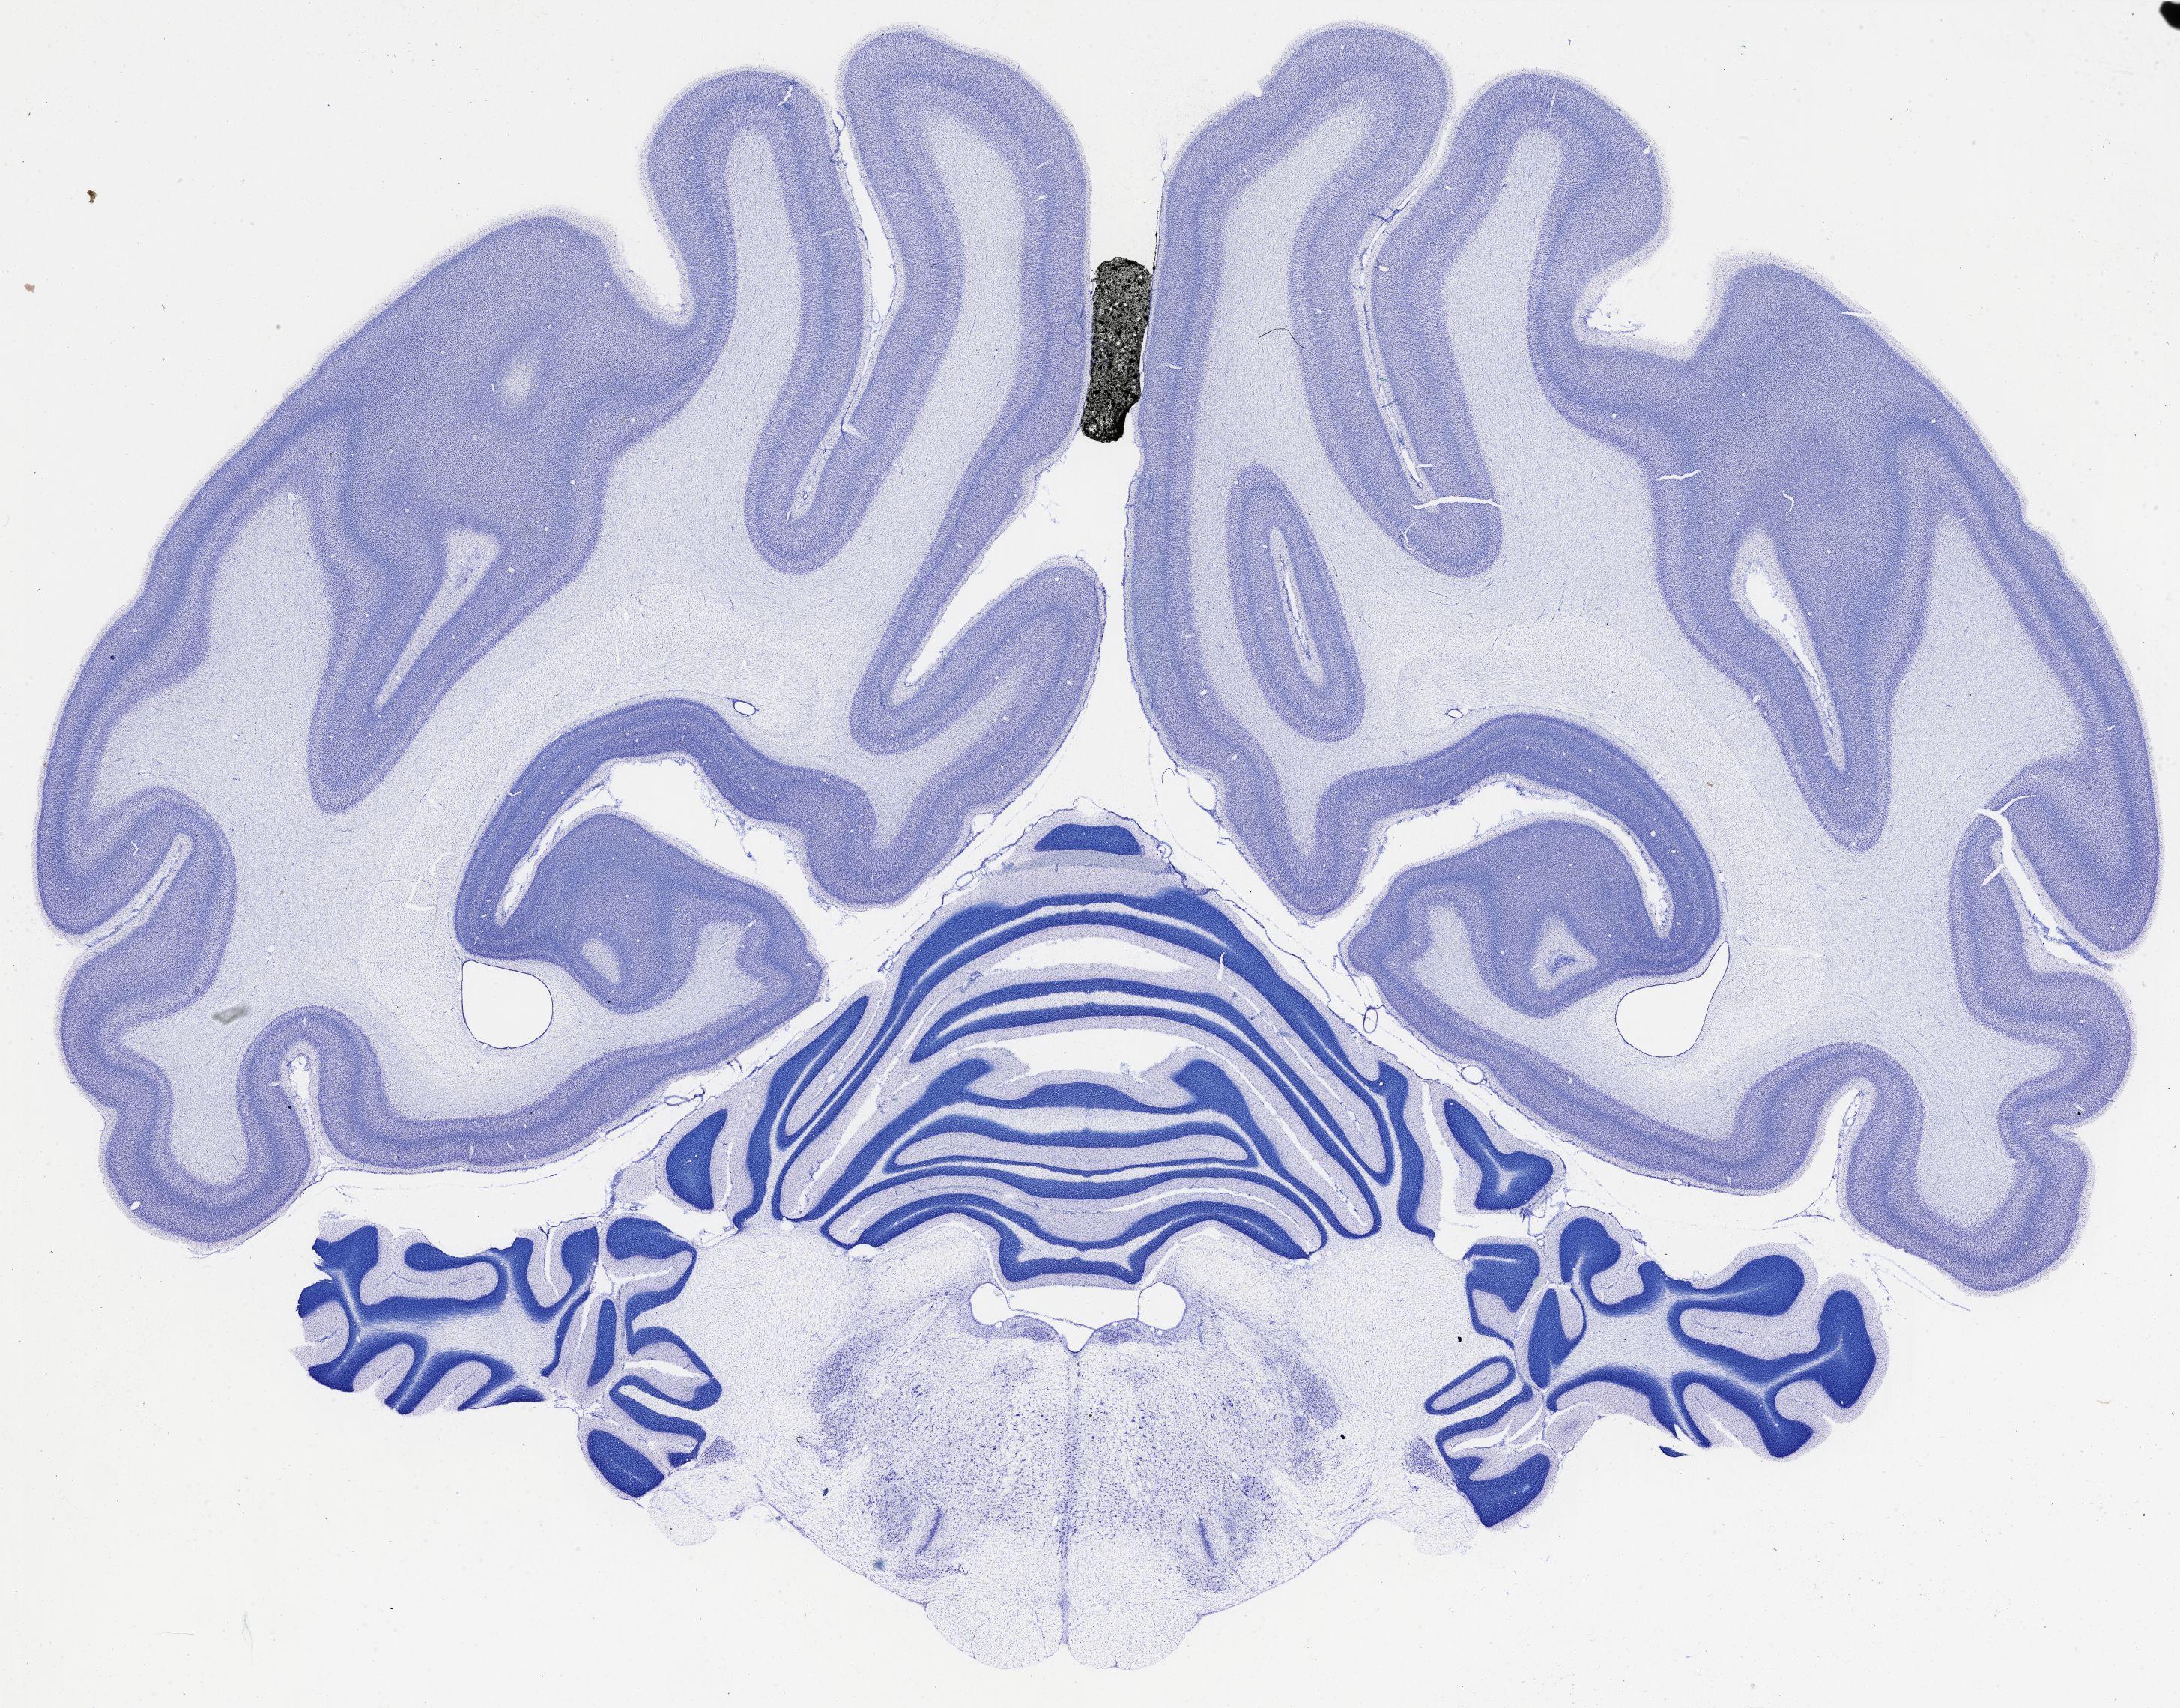

thumbnail

521